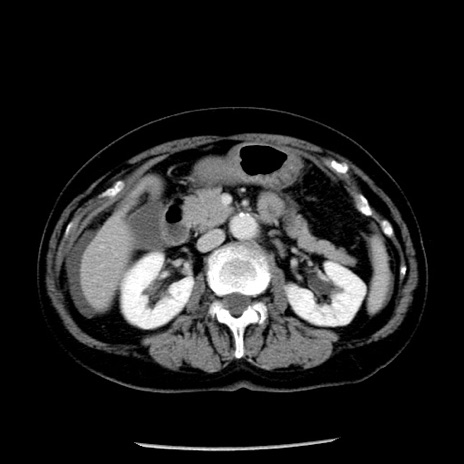

症例13(横断像)

【症例】70歳代女性

【主訴】腹痛、嘔吐

【現病歴】15時間程前(昨晩)より腹痛あり。今朝になっても症状の改善なく、嘔吐あり。腹痛も増悪あり、救急外来受診。

【既往歴】子宮癌全摘術後

【身体所見】意識清明、BP 121/72mmHg、P 74bpm、SpO2 100%(RA)、腹部:平坦・軟、腸雑音ほぼ聴取せず。下腹部・心窩部・臍左上に圧痛あり。反跳痛なし。

【データ】WBC 10600、CRP 0.15